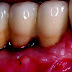

As a result of cell death in reaction to chemo- or radio-therapy, the mucosal lining of the mouth becomes thin, may slough off and then become red, inflamed and ulcerated. The ulcers may become covered by a yellowish white fibrin clot called a pseudomembrane. Peripheral erythema is usually present. Ulcers may range from 0.5 cm to greater than 4 cm. Oral mucositis can be severely painful. The degree of pain is usually related to the extent of the tissue damage. Pain is often described as a burning sensation accompanied by reddening. Due to pain, the patient may experience trouble speaking, eating, or even opening the mouth.

Diagnosis is based on the symptoms the patient is experiencing and the appearance of the tissues of the mouth following chemotherapy, bone marrow transplants or radiotherapy. Red burn-like sores or ulcers throughout the mouth is enough to diagnose mucositis.